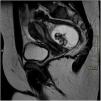

Se completó el estudio con una ecografía abdominal (fig. 2) que mostró una lesión de 73×70×58mm, compatible con teratoma, sin poder especificar el órgano del que dependía. Se realizó también una resonancia magnética abdominal (fig. 3).

Los tumores ováricos son raros en pediatría, representando entre el 1-5% de los tumores infantiles. Hasta el 90% de estos tumores son germinales, siendo el más frecuente el teratoma maduro (55-70% de las neoplasias ováricas en pediatría)1,2. El teratoma maduro ovárico es una entidad benigna que puede aparecer a cualquier edad, pero la prevalencia más alta se da en mujeres en la segunda y tercera década de la vida. Proviene de al menos 2 de las 3 capas de células germinales, siendo lo más habitual encontrar tejidos del ectodermo (pelo, grasa, dientes, piel…)2. La mayoría de las pacientes están asintomáticas al diagnóstico, encontrándose como un hallazgo casual en las pruebas de imagen, pero pueden presentar dolor abdominal, masa palpable en la exploración, complicaciones como la torsión o la rotura ovárica e incluso síndromes paraneoplásicos, aunque esta manifestación es muy rara. Hasta un 10% de los casos pediátricos pueden ser bilaterales3. El diagnóstico inicial se realiza mediante ecografía abdominal, siendo la imagen más común la de una lesión quística con un nódulo ecogénico compuesto de pelo, grasa o hueso, que suele presentar sombra acústica posterior (nódulo de Rokitansky). Habitualmente se completa el estudio con una resonancia magnética para delimitar mejor su tamaño y relación con estructuras vecinas2. Alrededor del 50% pueden tener calcificaciones y hasta en un 22% se pueden objetivar piezas dentarias radiológicamente4. Por ello, el hallazgo de imágenes con densidad calcio y forma de pieza dentaria en una radiografía de abdomen pueden ser clave en el diagnóstico de teratoma.